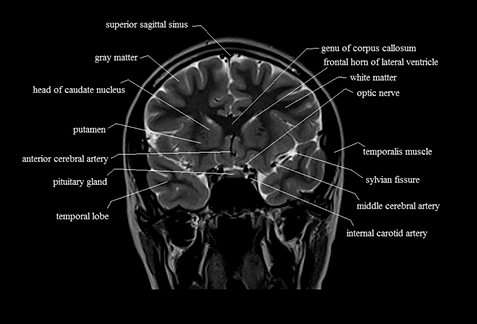

This is the coronal brain. In this slice, 15 parts of the brain are visualized. Can you identify the missing part in this slice ?